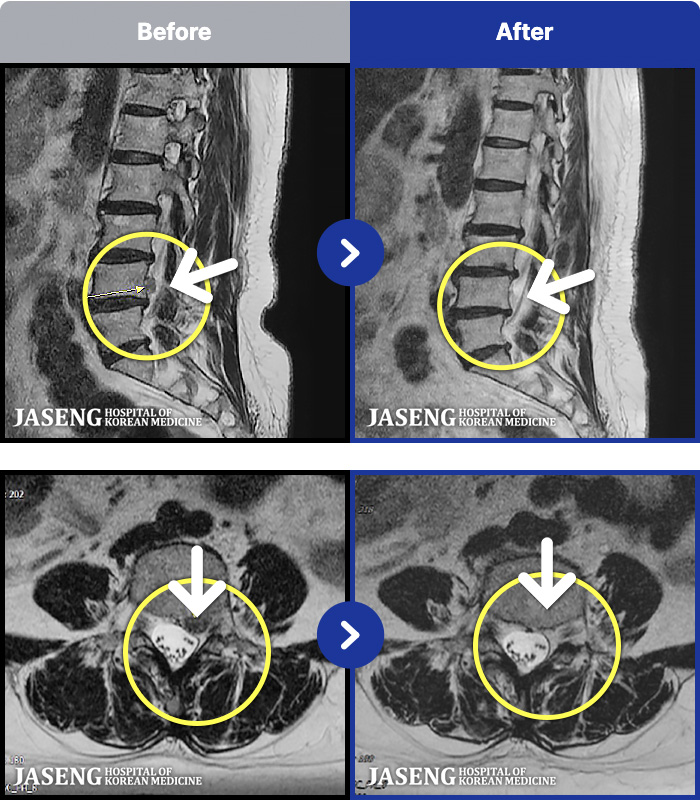

- MRI ġ

MRI ġ

1,240 MRI ũ ʸ Ȯϼ.